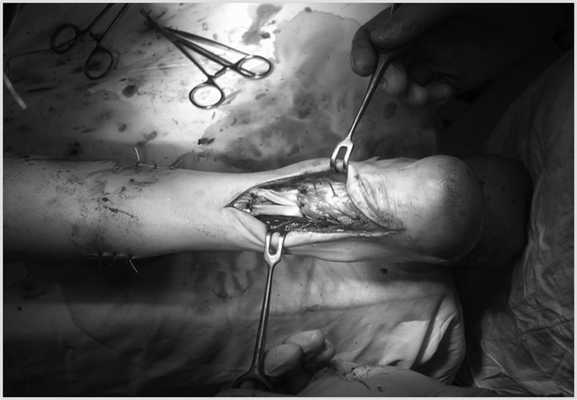

Выполнен доступ к дефекту ахиллова сухожилия и его дистальному концу. Дистальный конец выделен от рубцов. Дефект ахиллова сухожилия визуализирован (рис. 3). Рис. 3. Выделение дистального конца ахиллова сухожилия.

Выполнен линейный разрез кожи длиной 3 см по наружной поверхности в средней трети голени для выделения сухожилия короткой малоберцовой мышцы (рис. 4). Рис. 4. Выделение сухожилий короткой малоберцовой мышцы.

Далее выполнен разрез длиной 3 см по внутренней поверхности в средней трети голени для выделения сухожилия задней большеберцовой мышцы (рис. 5). Рис. 5. Выделение сухожилия задней большеберцовой мышцы.

После выделения сухожилия короткой малоберцовой мышцы и сухожилия задней большеберцовой мышцы проводятся подкожно и выводятся в зону дефекта. Далее в оптимальном натяжении сухожилия прошиваются к дистальному концу ахиллова сухожилия (рис. 6). Рис. 6. Транспозиция сухожилий короткой малоберцовой и задней большеберцовой мышц к дистальному концу ахиллова сухожилия.